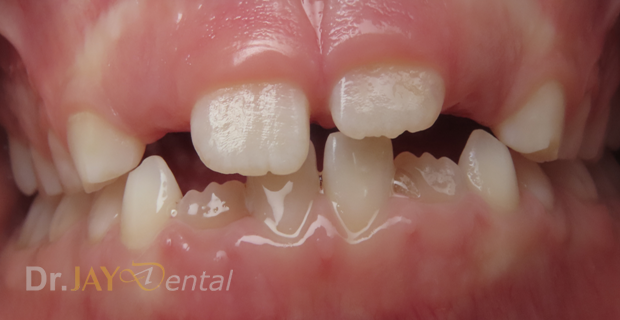

CASE 21

Crowding of teeth, misaligned

Crowding resolved –happened in 6 months, no wires or brackets on teeth